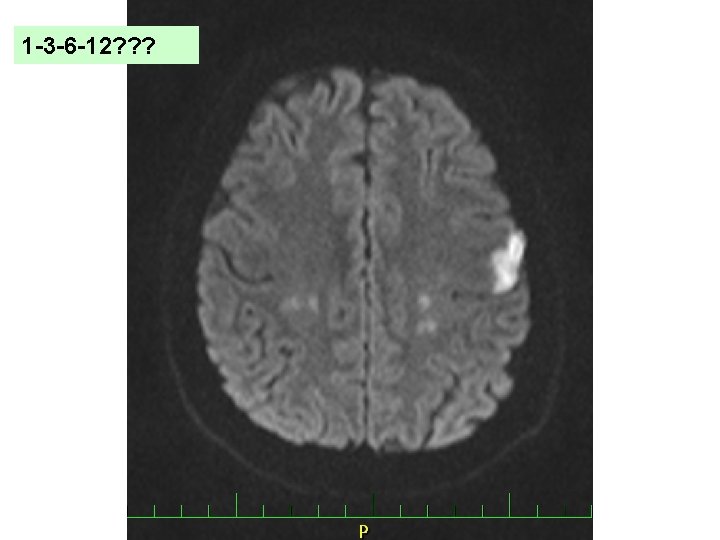

“ 1 -3 -6 -12 rule” (EHRA) Závažnost CMP Zahájení NOAC TIA 1. den Mild stroke NIHSS <8 Moderate stroke NIHSS 8 -16 Severe stroke NIHSS >16 3. den 6. den 12. dnů Heidbuchel H et al. EHRA Guidelines. Europace 2015.

Nevýhody pravidla “ 1 -3 -6 -12” Závažnost CMP Zahájení NOAC TIA 1. den Mild stroke NIHSS <8 Moderate stroke NIHSS 8 -16 Severe stroke NIHSS >16 3. den 6. den 12. dnů Heidbuchel H et al. EHRA Guidelines. Europace 2015.

? – č. 6 �Klasifikujte následující ikty na snímcích: a) Mild b) Moderate c) Severe

? – č. 7 �Klasifikujte následující ikty na snímcích: a) Mild b) Moderate c) Severe

Základní faktory rozhodnutí? Velikost ischemie na kontrolním CT Prokrvácení ischemie? Přítomnost leukoaraiózy na MR/CT Vstupní NIHSS a NIHSS za 24 h Microbleeds na MR Zahájení antikoagulace 1 -3 -6 -12 Hypertenze Plán. operace